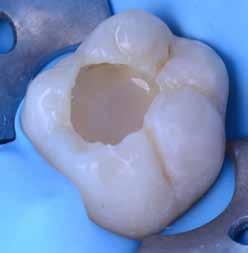

Az 53 éves hölgy páciens jobb felső 6-os fogában látható amalgámtömés cseréje volt a cél. A tömés mellett secunder caries és az amalgám következtében létrejött mesialis zárólécen áthaladó repedés, továbbá mesialis caries figyelhető meg (1. ábra). El kellett kerülni, hogy a tömés kifúrásakor az amalgámtörmelék a páciens szájába kerüljön, esetleg ebből valamennyit lenyeljen, a kezelés első lépésként kofferdám izoláció került fel a jobb felső kvadránsba (2. ábra). A kapocs a 1.7 fogra került, ezzel kényelmesen helyet teremtett a későbbiekben felkerülő matricarendszernek. Az egyszerre több fog izolálása lehetővé teszi, hogy a szomszédos fogak referenciául szolgáljanak a restauráció felépítése közben.

A régi amalgámtömés eltávolítását követően caries indikátor segítette a carieses laesio megfelelő kitisztítását a pulpa expozíciója nélkül. Ezután kerülhetett sor az ideális üregdesign kialakítására, továbbá a zománcszélek finírozására (3. ábra) Az approximális box megnyitása során az alátámasztatlan zománcprizmák eltávolításra kerültek, ezzel is csökkentve a secunder caries képződés veszélyét. Az így kialakuló forma elősegíti a matrica megfelelő adaptációját, végül pedig az approximális box határainak a hozzáférhetőségét, így finírozás során ez jobban kontrollálható és polírozható.

A Palodent V3 matricarendszer felhelyezését követően a zománc 10 másodperces szelektív savazása, majd lemosása és leszárítása után történt a kavítás bondozása Prime & Bond Universallal.

Kulcslépés: a II. osztályú üreget a matricarendszer segítségével I. osztályúvá lehetett átalakítani.

A pontosabb széli záródás érdekében célszerű a matrica illesztési határába némi folyékony kompozitot felvinni (NeoSpectra ST flow A2), majd megvilágítás nélkül a zárólécet paszta kompozittal (NeoSpectra STHV A2) felépíteni, miközben a kifolyó fölösleges folyékony kompozit eltávolításra kerülhet. Így ki lehetett használni és kombinálni a két különböző konzisztencia előnyeit.

A polimerizációt követően kerülhet sor a matricafeszítő gyűrű, valamint a matrica eltávolítására. A Palodent V3 fülekkel ellátott matrica kialakításának és a speciális PinTweezers csipesznek hála, a feszes kontaktpont ellenére a matrica könnyedén eltávolítható. Az éket viszont a kezelés végéig

célszerű bennhagyni, elkerülve egy esetleges nemkívánatos vérzést (4. ábra)

A matrica és gyűrű nélkül az approximális fal magassága, valamint a szomszédos fogakhoz viszonyítható dimenziók jobban megállapíthatóak. A jobb térlátás és a nagyobb mozgástér precízebb eredményhez vezet, csökkentve ezzel az utólagos finírozás mértékét, továbbá a részletgazdagon kialakított anatómiai struktúrák torzulásának az esélyét. Az üreg mélyebb részei SDR Plus A3-mal kerültek feltöltésre, majd NeoSpectra STLV A3-mal kiegészítve vált teljessé a dentin pótlása (5. ábra), ezzel létre lehetett hozni egy homorú formájú kromatikusabb alapot.

Ezt követően csücsökről csücsökre haladva a felső hatosokra jellemző anatómiai struktúrák, megfelelő orientációval bíró csücsöklejtők és elsődleges barázdák Neo Spectra

HV A2 anyagból kerültek kialakításra (6. ábra). Apró „kompozit-hurkákkal” kiegészítve létrehozható a csücskökön belüli tagoltság, ezzel kialakítva a másodlagos barázdarendszert és egy sokkal kidolgozottabb anatómiai struktúrát (7. ábra). A fogorvos esetleges „művészi hajlamát” is figyelembe véve, a természethű megjelenés barázdafestéssel (Micerium - Stain Brown 2) még tökéletesebb lehet (8. ábra). Ezzel a korábban részletgazdagon kialakított ba-

rázdarendszer kiemelhető, és optikailag fokozható a gödröcskék mélysége is.

A restauráció megfelelő polimerizációja után célszerű a kofferdám nyújtotta retrakciót kihasználni, és a restauráció széli záródásában levő esetleges kompozitfölösleg elfinírozását jobb rálátás mellett elvégezni (9. ábra). Ebben nagy segítségünkre lehet az Enhance rendszer, mely a kompozitot nagyon szépen elsimítja, de a természetes fogszövetet nem bántja.

A matricázott terület széli záródásának a kidolgozásában az EVA polírozó (10. ábra) lehet a segítségünkre, amellyel a gingiva sérülése megelőzhető, és a kialakított feszes kontaktpont sem kerül redukcióra (11-12. ábra)

A kofferdam eltávolítását követően kerülhetett sor az occlusio beállítására csücsöklejtők domborúságának a redukciója révén (13. ábra). A harapás gyémántfúrókkal történő beállítása után a polírozás Enhance rendszerrel történt, melynek végső lépéseként a PrismaGloss használatával (14. ábra) nyerhette el a restauráció a végső fényességét (15. ábra)

A ma rendelkezésre álló modern eszközöknek és anyagoknak hála II. osztályú üregek direkt módon kiszámíthatóan restaurálhatóak. A matricarendszernek köszönhetően helyreállítható a feszes kontaktpont, a „kaméleon effektussal” bíró kompozit pedig a tömés integrációjáért felel. A megfelelő adhézió, a precízen kidolgozott széli záródás és a plakkréteg megtapadását nehezítő polírozott felszín a kezelés hosszú távú sikerének a garanciája. Mindezek együtt egy hosszú távon tartós, funkcionális és esztétikai rehabilitálást tesznek lehetővé.